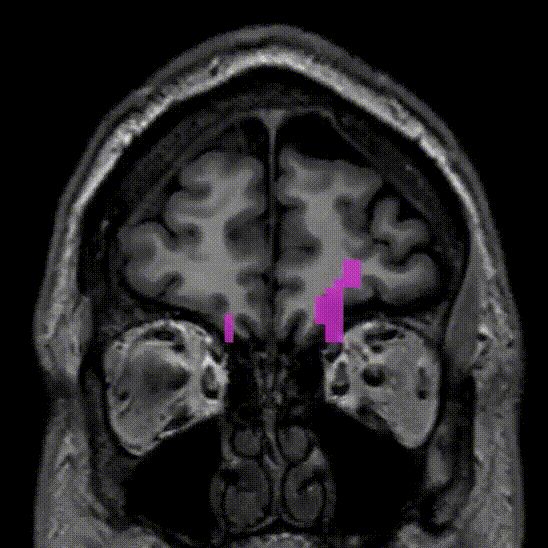

Corticospinal tract. Most important projection fiber tract. Contains motor and sensory fibers from pre-motor, precentral (primary motor) and post-central cortices via the posterior limb of the internal capsule all the way to the spinal cord. Most fibers decussate in the medulla.

Damage to the corticospinal tract can cause permanent motor damage! Especially damage to pre-central fibers.